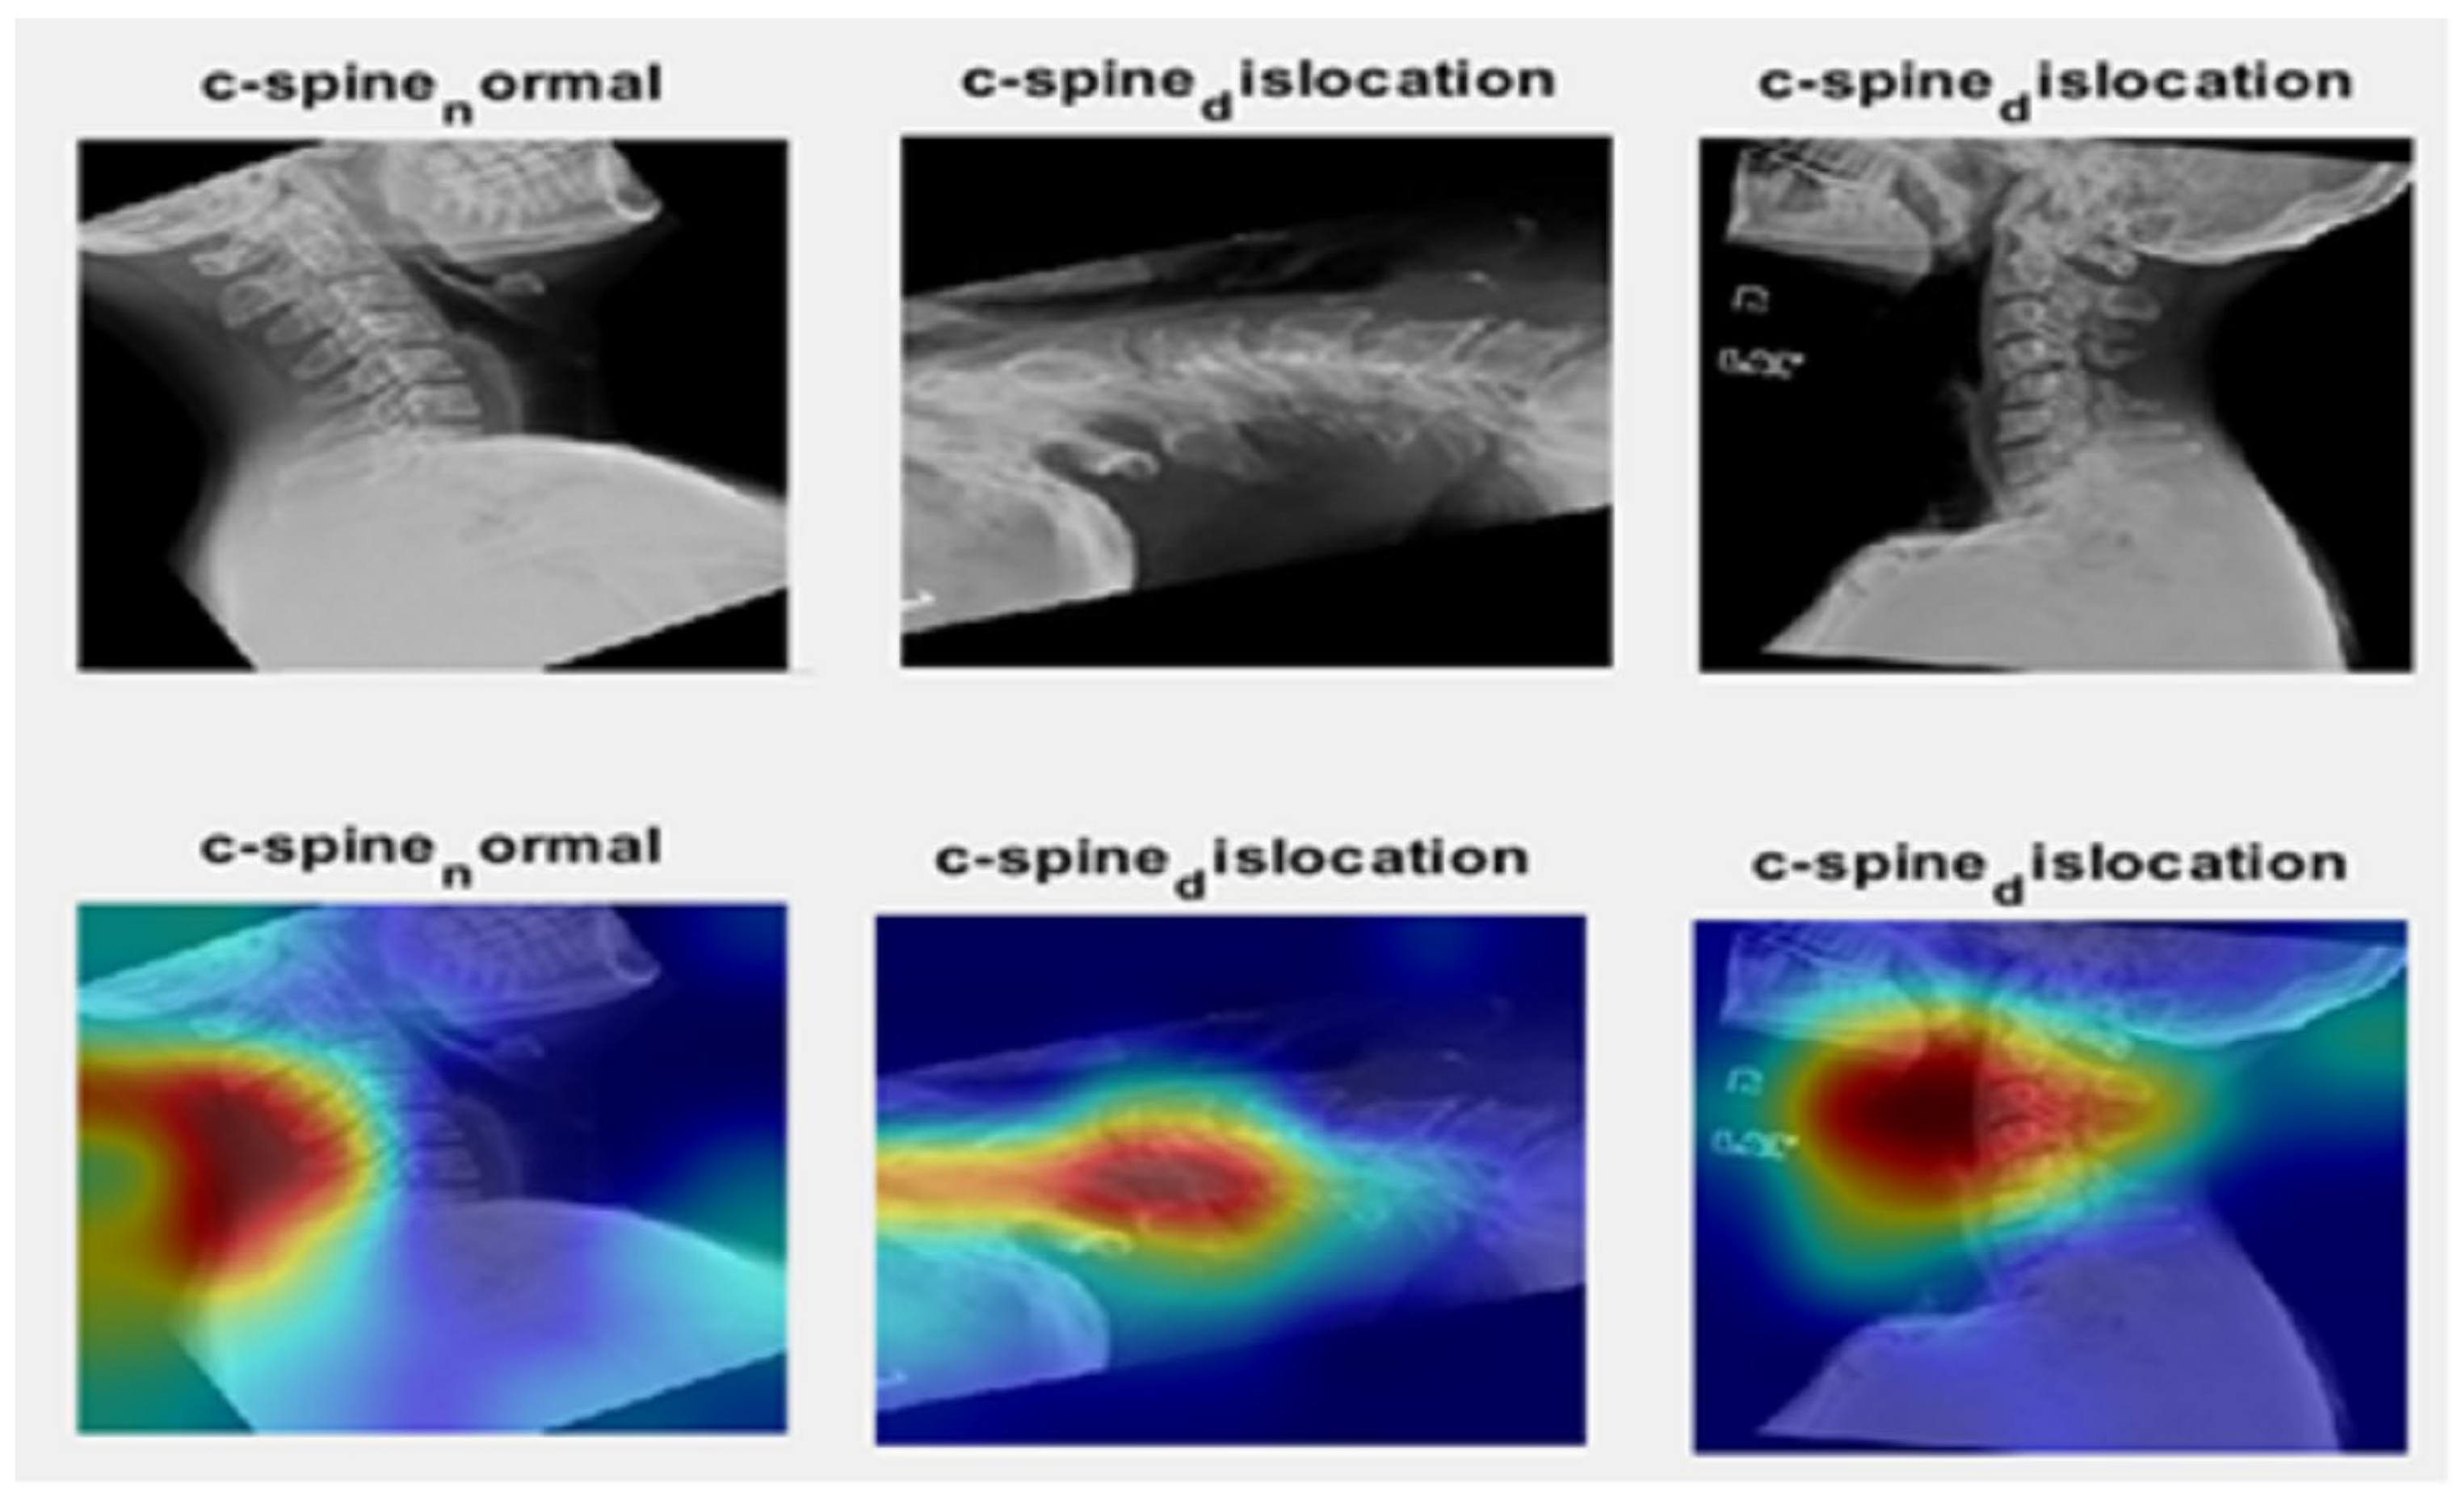

- The ability of the proposed model to successfully detect the cervical spine was proven by the saliency map.

4.1.3. Saliency Map